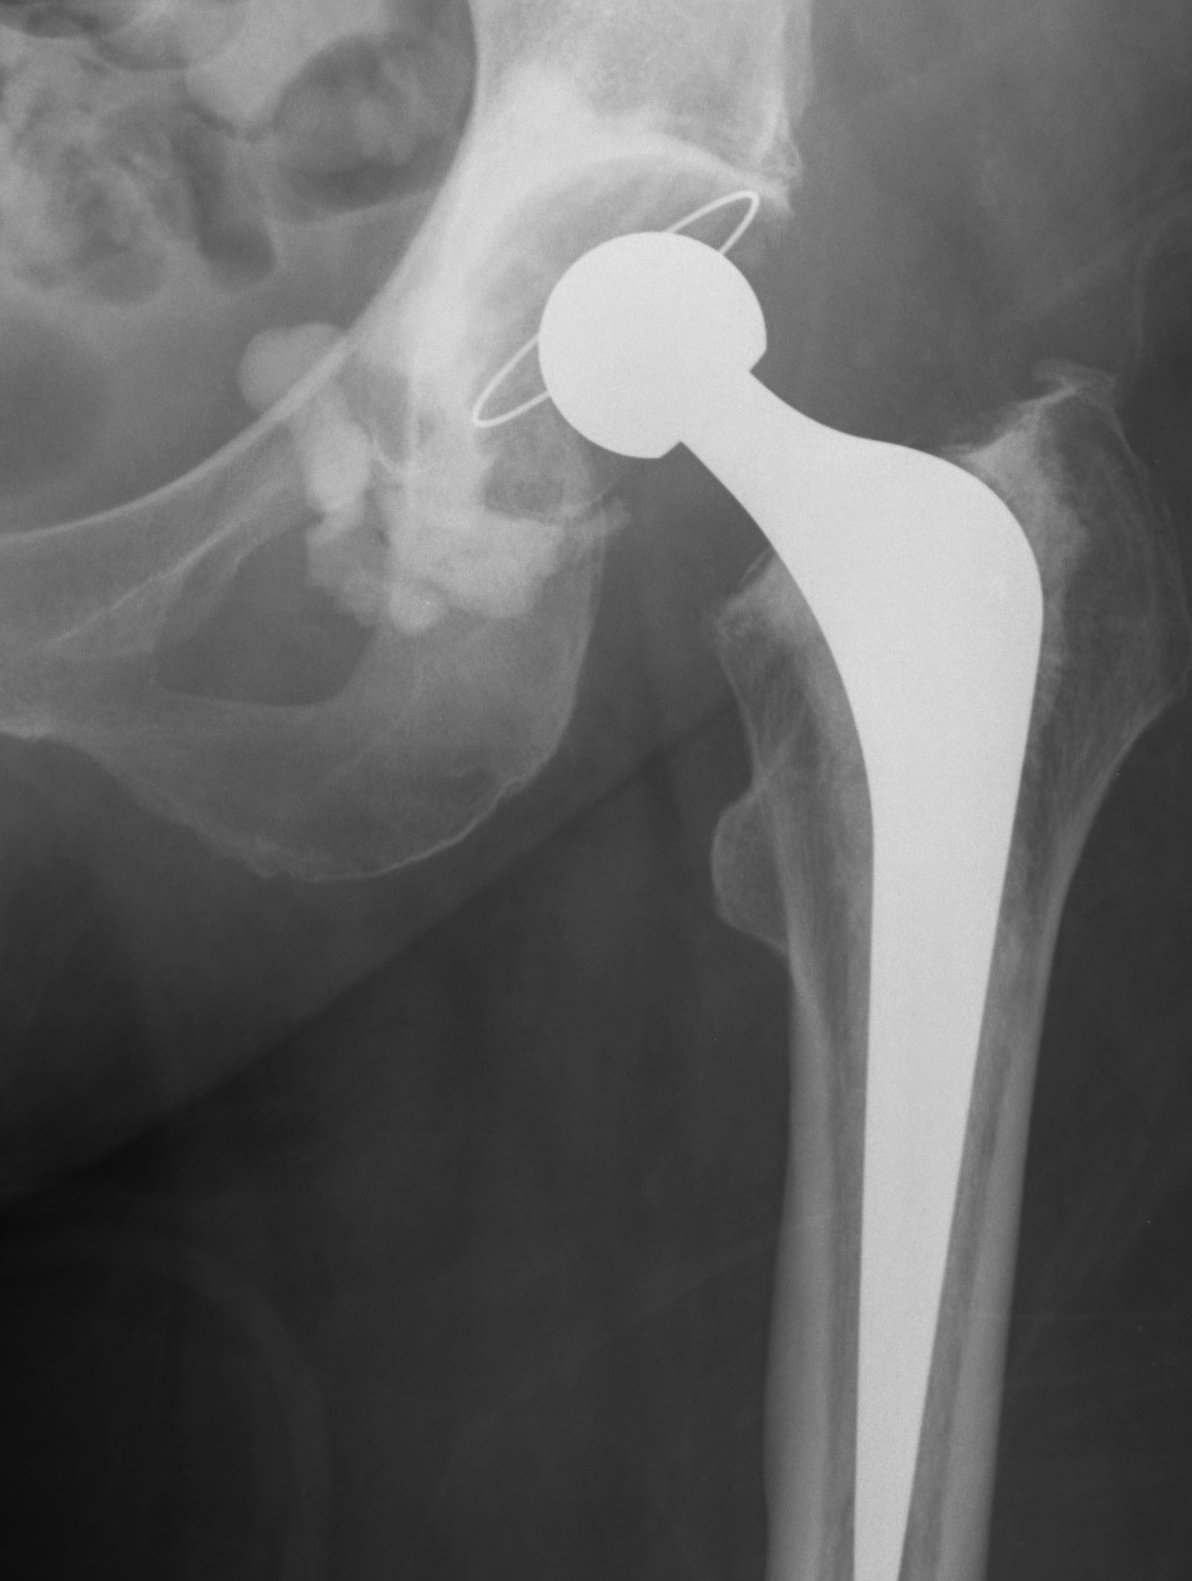

Loosening

Signs

- obvious migration in comparison previous films

- cement mantle fracture

- progressive > 2 mm lucency

Charnley zones

1 - superior 1/3

2 - middle 1/3

3 - inferior 1/3